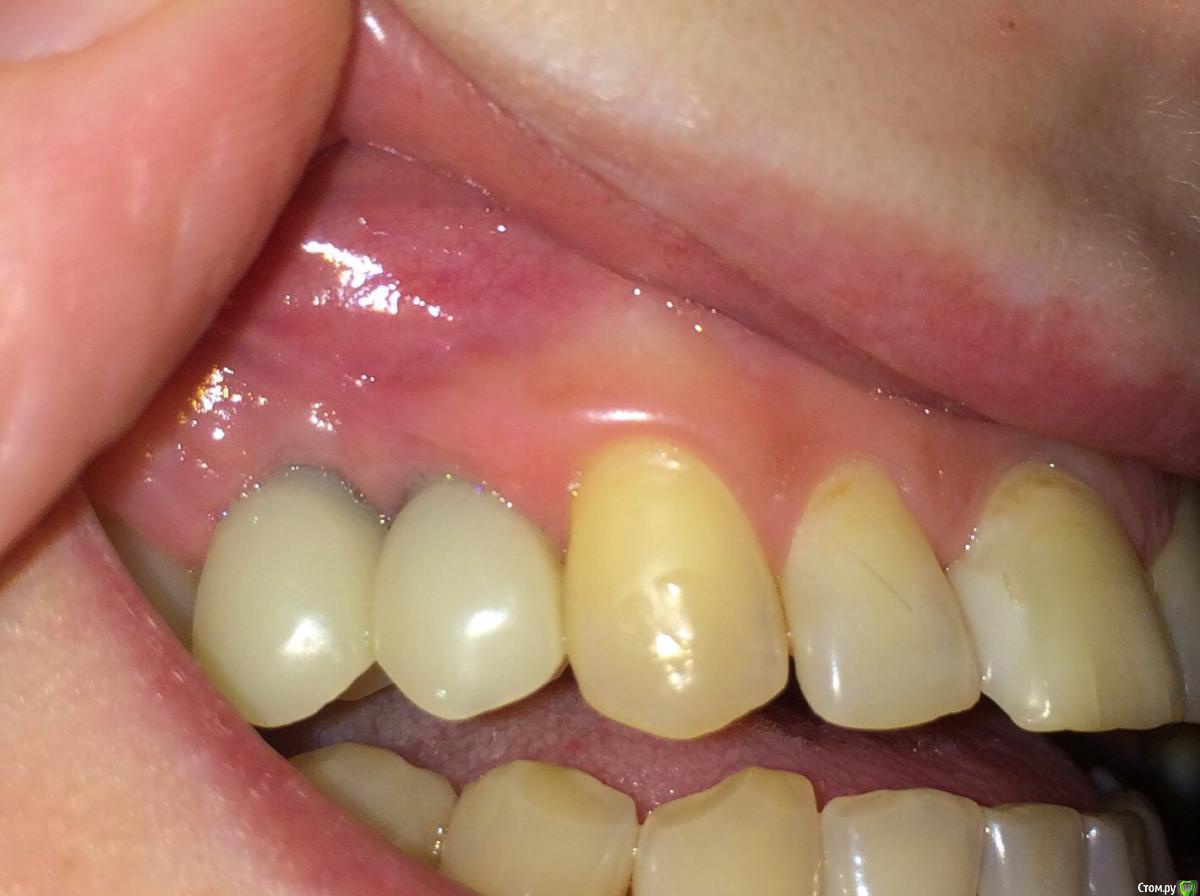

Nadiakroha Опубликовано 14 февраля, 2015 Автор Поделиться Опубликовано 14 февраля, 2015 выкладываю фото, обвела пунктиром место наращенной десны. Извините, что столько времени у Вас отнимаю! Ссылка на комментарий

Nadiakroha Опубликовано 14 февраля, 2015 Автор Поделиться Опубликовано 14 февраля, 2015 (изменено) выкладываю фото, обвела пунктиром место наращенной десны. Извините, что столько времени у Вас отнимаю!Временные коронки стояли до операции по наращиванию, после заживления, через 10-12 дней поставили те же коронки, немного их подкорректировав, то есть сделали более естественную форму.. Вот фото коронок, до наращивания. Изменено 14 февраля, 2015 пользователем Nadiakroha Ссылка на комментарий

SDC Опубликовано 14 февраля, 2015 Поделиться Опубликовано 14 февраля, 2015 (изменено) выкладываю фото, обвела пунктиром место наращенной десны. Если так и есть, то это не тот регион, где необходимо увеличение объема.Трансплантированные ткани с бугра в.ч. действительно долго растут. И через год будет прирост, и через 2, но я сомневаюсь, что рост будет там, где нужно для эстетики. А зачем, в таком случае, снимали временные коронки? Насколько я вижу, трансплантация была на расстоянии от них? Изменено 14 февраля, 2015 пользователем SDC 1 Ссылка на комментарий

Nadiakroha Опубликовано 15 февраля, 2015 Автор Поделиться Опубликовано 15 февраля, 2015 Доку вообще все понравилось, и его не смутили 2 "сросшихся" кривых зуба и я просила его исправить ситуацию, так как при улыбке у меня открываются боковые зубы больше,чем даже передние.. Спасибо, за честный ответ! вы подтвердили мои мысли о том,что операция была бесполезна, и что дело все в неправильно подобраном имплантате.. высылаю фото до удаления зуба,чтоб не быть голословной,и что у меня был нормальный сосочек (зуб 1,5 с металлокерамикой) Ссылка на комментарий

Nadiakroha Опубликовано 16 февраля, 2015 Автор Поделиться Опубликовано 16 февраля, 2015 Если так и есть, то это не тот регион, где необходимо увеличение объема.Трансплантированные ткани с бугра в.ч. действительно долго растут. И через год будет прирост, и через 2, но я сомневаюсь, что рост будет там, где нужно для эстетики. А зачем, в таком случае, снимали временные коронки? Насколько я вижу, трансплантация была на расстоянии от них? видимо промахнулась она немного... Все понимаю, со всеми бывает.. Но можно же признать и переделать бесплатно?! Мне предлагают снова 10000 отдать за новое наращивание.. Ссылка на комментарий

Mane Опубликовано 16 февраля, 2015 Поделиться Опубликовано 16 февраля, 2015 Вы сами ответили на вопрос - пластика не удалась. А это самое главное. Нужно чтобы удалась. Тогда и будут изменения. Чисто механического здесь решения нет - открутить/закрутить/прибить и тд. Ссылка на комментарий